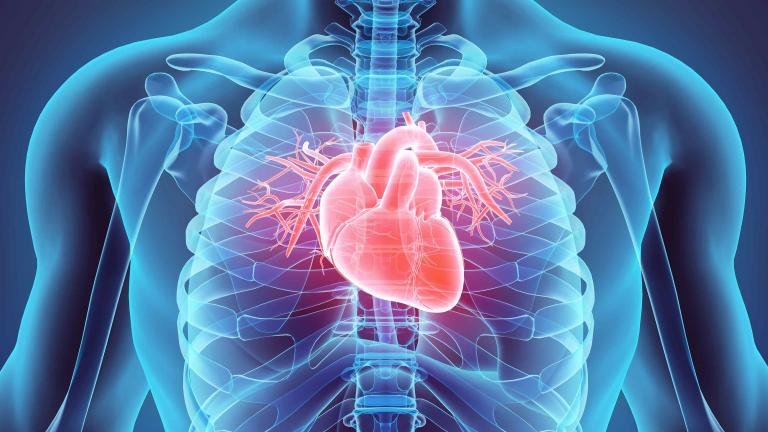

Dr. Ashleys Limited, based in the vibrant heart of Hong Kong, is deeply committed to transforming cardiovascular health. Cardiovascular diseases remain a pressing global concern, requiring a comprehensive approach that encompasses prevention, management, and education. Our unwavering commitment extends beyond business; it’s about impacting lives, making a meaningful change, and leaving behind a legacy of healthier hearts.

Our journey in cardiovascular care began with our pioneering product, —an emblem of our dedication to combat cardiovascular diseases. Today, we take pride in our place within the Hong Kong and international cardiovascular segments, where our brands are recognized for their commitment to advancing cardiac healthcare.

Our commitment transcends medications. We understand that effective cardiac care encompasses a comprehensive approach. Dr. Ashleys Limited offers a range of medical devices and equipment tailored for cardiac patients. Our products aid in diagnosis, monitoring, and treatment, empowering patients to lead healthier lives.

Our heart-centric approach places patients at the core of our mission. We believe that compassionate care is a critical component of the journey to recovery and well-being. Dr. Ashleys Limited not only equips patients and healthcare professionals with the tools but also imparts knowledge and support essential for improving cardiac health.